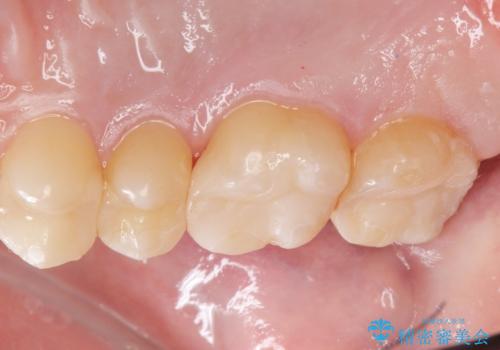

- 銀の詰め物をやりかえたいとの事で来院。

詰め物を外し、虫歯がない事を確認してからe-maxインレーで治療しました。

白く、適合の良い詰め物が入りました。セラミックは汚れや細菌付着しにくいので虫歯の再発のリスクが低くなります。